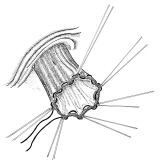

器械吻合器テクニックあれこれ

あのころ、実用化されたばかりの自動吻合器の使用上の「コツ」シリーズ。